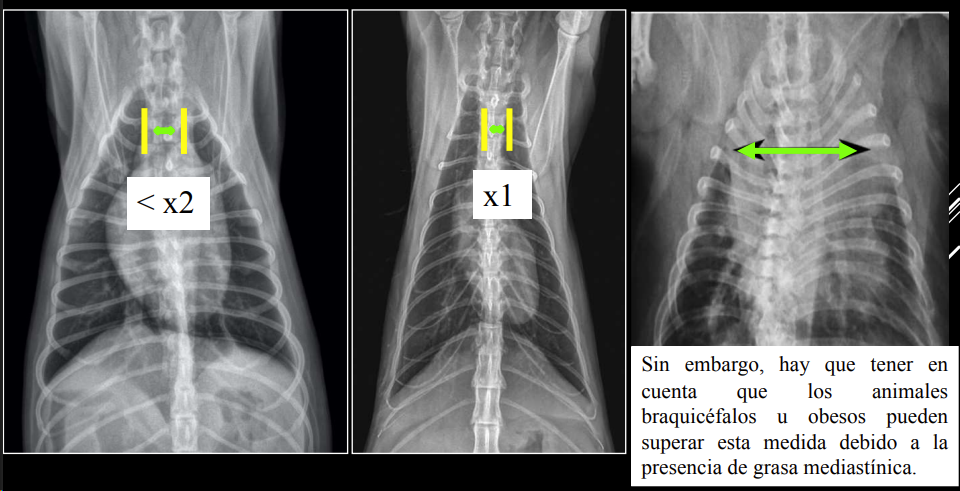

3. Alteraciones de anchura del mediastino craneal

- En perros: anchura < 2x VT.

- En gatos: anchura ≈ VT.

- En braquicéfalos/obesos puede verse mayor (grasa mediastínica).